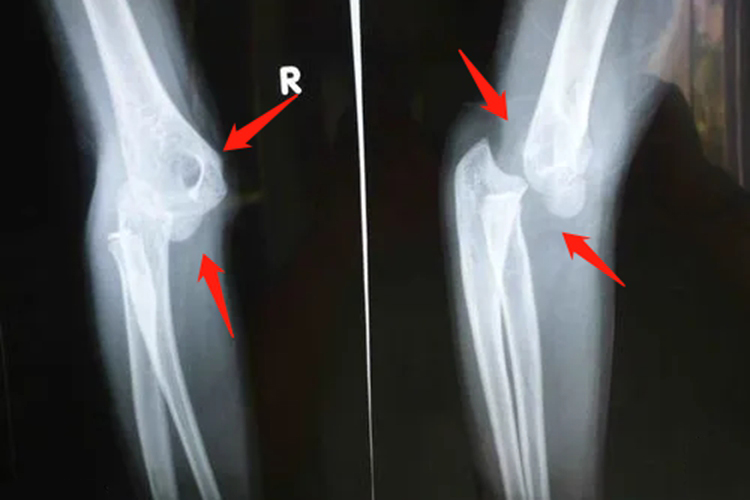

肘关节脱臼

婴儿肘关节脱臼会有肘部肿胀、畸形、疼痛,肘关节功能障碍,依旧会有哭闹。外观可见肘窝部饱满,前臂外观变短,尺骨鹰嘴后突,肘后部空虚和凹陷。关节弹性固定于120°-140°,肘部三点关系完全破坏。常见的畸形包括呈靴形畸形,肘内翻、肘外翻畸形,肘关节出现内收、外展功能障碍,肘部左右径增宽,肘关节过伸,屈曲受限。